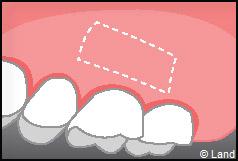

Destinées aux zones esthétiques, elles consistent à prélever la partie profonde du palais (site donneur).